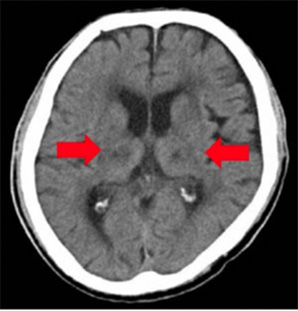

アルツハイマー病

脳血管性認知症

VSRAD(ブイエスラド)

早期アルツハイマー型認知症診断支援システム

認知症を早期に画像で診断できます。